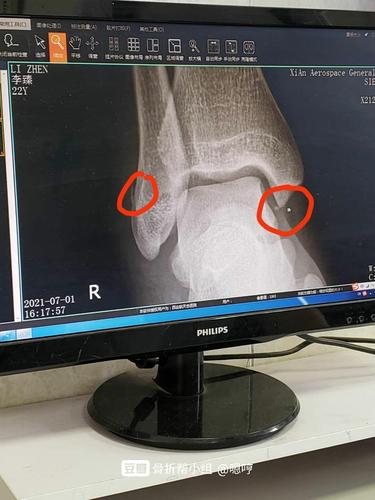

脚骨折片子,骨折片子

到医院拍了片子,医生说骨折了,片子显示右脚踝骨折两处.